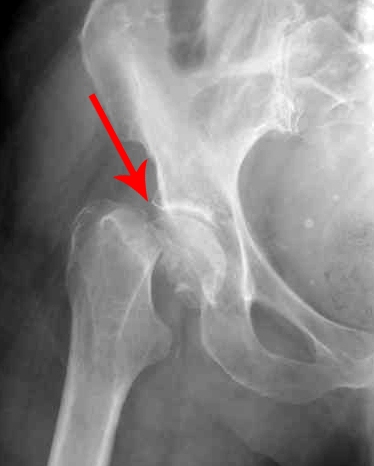

Точный диагноз перелома шейки бедренной кости («шейки бедра») можно поставить по данным рентгенограмм. В некоторых случаях для уточнения характера смещения фрагментов может понадобиться компьютерная томография.

Рентгенограмма перелома шейки бедренной кости